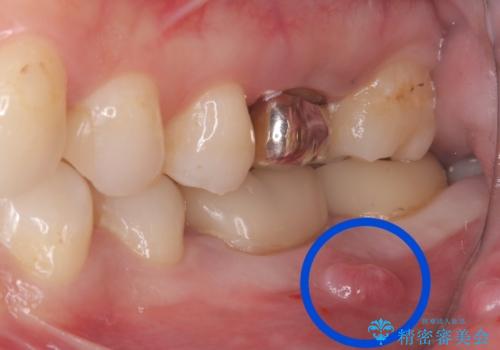

- 主訴:左下6番目の歯の周りが痛くなり、他院で診てもらったが抜歯と言われてしまった。ネットで歯牙移植というものを知りやっている医院を探している。

左下6番目の歯の周りに大きく透過像を認め、再根管治療後の予後が良くない可能性が大きく当院でも抜歯適用歯と説明しました。欠損部に対しインプラント治療や歯牙移植(左下の親知らずの移植)、ブリッジを提案し、歯牙移植を行うこととなりました。